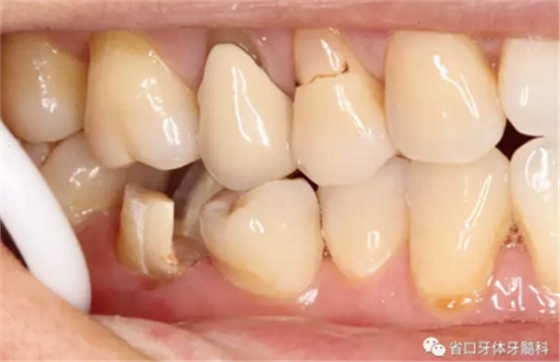

圖4 牙體預備后頰側觀